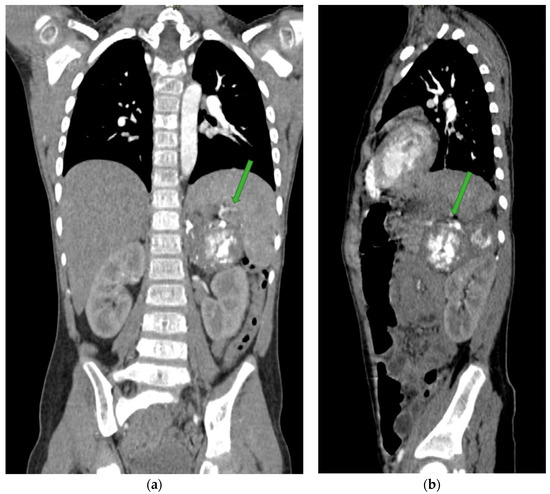

4. Case Presentation

5.3. Imaging